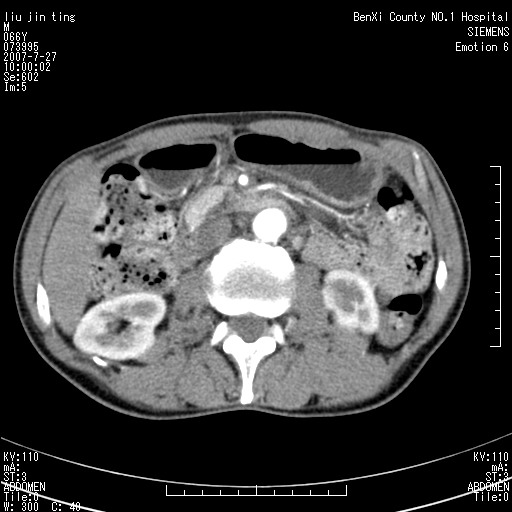

腹痛,背痛,无恶心呕吐,不黄,彩超示胰腺钩癌,ct扫描病灶平扫30-40hu,增强后动脉期40--60hu,静脉期50-68hu,真的是钩突上的么?您要试一试么?

沿着肠系膜上动脉呈匍匐性生长的软组织肿块,形态不规则,包绕肠系膜上动脉,呈明显强化,考虑来源于肠系膜的恶性肿瘤

沿着肠系膜上动脉呈匍匐性生长的软组织肿块,形态不规则,包绕肠系膜上动脉,呈轻-中度强化,考虑来源于肠系膜的恶性肿瘤。

钩突是正常的,只见腹膜后淋巴结的肿大,考虑淋巴瘤或转移可能。

支持!恶性纤维组织细胞瘤可能,与淋巴瘤及淋巴结转移鉴别(腹主动脉周围清晰,其他部位亦未见明显肿大淋巴结)。